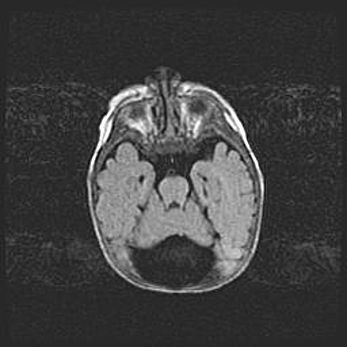

Мальформация Денди-Уокера. Киста задней черепной ямки.

Агенезия мозолистого тела.

Возраст: 2,5 месяца

Вес: 2420 г

Пол: женский

Окружность головы: 37 см

Срок гестации: 32 недели

Мальформация Денди—Уокера — редкий вид патологии ЦНС, представляющий собой врожденный порок развития каудального отдела ствола и червя мозжечка, ведущий к неполному раскрытию срединной (Мажанди) и латеральных (Лушка) апертур IV желудочка мозга. Для этогно синдрома характерна триада симптомов: гипотрофия червя мозжечка и/или полушарий мозжечка, кисты задней черепной ямки, гидроцефалия различной степени. В 70% случаев порок сочетается и с другими аномалиями головного мозга, в частности с агенезией мозолистого тела.